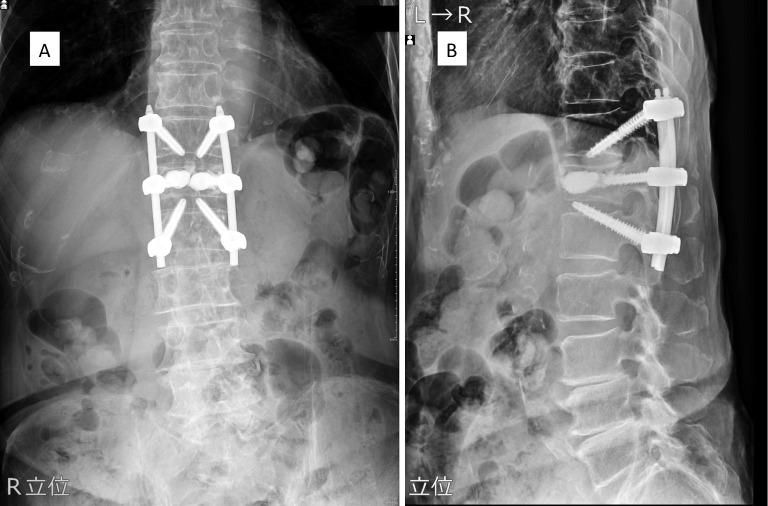

Percutaneous vertebral augmentation techniques, such as balloon kyphoplasty (BKP) and vertebral body stenting (VBS), are commonly used for surgical intervention in osteoporotic vertebral fractures (OVFs). However, markedly unstable OVF cases require additional fixation procedures, prompting the exploration of combined percutaneous vertebral augmentation and posterior fixation. A novel surgical approach involving percutaneous vertebral augmentation with upward penetrating endplate screws (PES) and downward PES, complemented by a short fusion of one above one below, was developed. This study aimed to introduce and report the preliminary outcomes of this technique based on a retrospective analysis of 20 consecutive cases in the short and medium term.

Surgical indications are a vertebral wedge angle difference of 10° or more, vertebral pedicle fractures, posterior wall fractures, and diffuse low-signal changes exceeding 50% on T1-weighted magnetic resonance imaging. The procedure is reserved for highly unstable cases following a comprehensive health assessment. The surgical technique involves prone positioning, fluoroscopy-guided percutaneous vertebral augmentation, and the use of downward PES in the cranial vertebral body and upward PES for the caudal vertebral body by percutaneous technique. The fixation range is one above and one below.

RESULTS

The case series of 20 patients, with an average follow-up period of 146.9 days, demonstrates a mean surgical time of 57 min and minimal complications. The advantages of the technique are as follows: ease of performance, minimal fixation range, and time efficiency. Risks, such as potential screw loosening and the need for prolonged follow-up, are acknowledged.

经皮椎体强化技术,如球囊椎体后凸成形术(BKP)和椎体支架置入术(VBS),常用于骨质疏松性椎体骨折(OVF)的手术干预。然而,明显不稳定的OVF病例需要额外的固定程序,这促使人们探索经皮椎体强化与后路固定相结合的方法。一种新的手术方法应运而生,该方法包括经皮椎体强化联合向上穿透终板螺钉(PES)和向下的PES,并辅以相邻椎体间的短节段融合。本研究旨在通过对20例连续病例的短期和中期回顾性分析,介绍并报告该技术的初步结果。

手术适应证为椎体楔角差10°或以上、椎弓根骨折、后壁骨折以及T1加权磁共振成像上超过50%的弥漫性低信号改变。该手术仅适用于经过全面健康评估的高度不稳定病例。手术技术包括俯卧位、透视引导下的经皮椎体强化,以及通过经皮技术在头侧椎体使用向下的PES,在尾侧椎体使用向上的PES。固定范围为相邻椎体。

结果

20例患者的病例系列,平均随访期为146.9天,平均手术时间为57分钟,并发症极少。该技术的优点如下:操作简便、固定范围小、时间效率高。同时也认识到存在潜在的螺钉松动等风险以及需要长期随访。